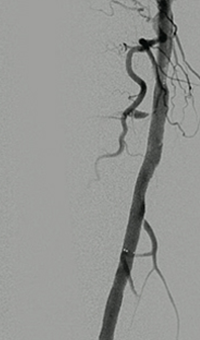

Thrombectomy of Occluded SFA - pre-procedure

Imaging SFA showing thrombus and calcification

Male in his late 40s presenting with pain in his right leg. An angiogram showed a total occlusion in the right superior femoral artery (SFA)

Thrombectomy of Occluded SFA - catheter positioning

Solent™ Proxi catheter positioned before the lesion

The physician delivered (antegrade) the Solent Proxi catheter to the proximal margin of the occlusion

Thrombectomy of Occluded SFA - thrombus removed

Thrombus removed following AngioJet™ treatment

After the third pass with Solent Proxi